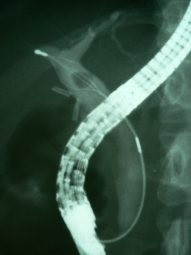

Coledocolitiasis con antecedente de colecistectomía por laparoscopía

Envíado por Dr. Carlos Miguel Zavaleta Consuegra